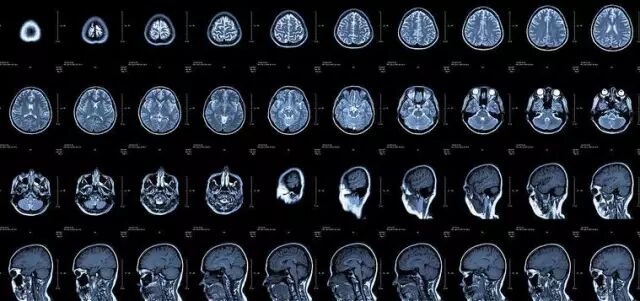

核磁共振:摇一摇再看

核磁共振机使用较强大的磁场,使人体中所有水分子磁场的磁力线方向一致,这时核磁共振机的磁场突然消失,身体中水分子的磁力线方向,突然恢复到原来随意排列的状态。简单说就相当于用手摇一摇,让水分子振动起来,再平静下来,感受一下里面的振动。所以,核磁共振(MRI)也被戏说为是摇摇看的检查。

颈椎病、腰椎间盘突出等椎间盘疾病需要观察椎间盘与相应的神经根,要想更好观察这些软组织,最优选择就是核磁。同样,对于关节、肌肉、脂肪组织检查,核磁也是首选。